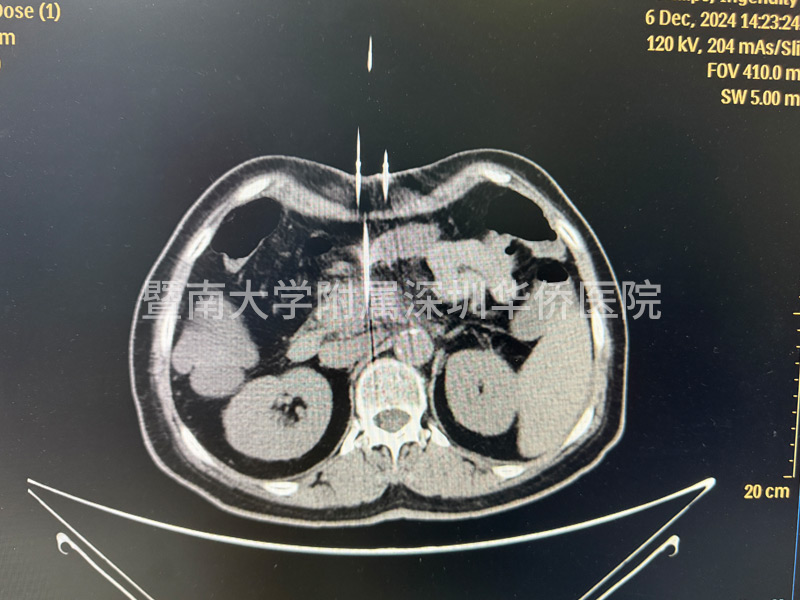

李女土的腫瘤在胰頭位置,大小為2.8*3釐米,已經包繞腸繫膜上動脈,失去了手術機會,在得知廣東省應用了國產奈米刀治療手術技術後,決定不遠千里來到深圳華僑醫院,接受奈米刀消融手術。

上午11點,李女士正式進入手術室,多位相關領域專家,透過國產研發的新型裝置正式對李女士進行手術,奈米刀消融技術適合中晚期的胰臟癌的治療,這臺手術裝置在產品設計中,具有全球領先的核心技術,實現了在消融過程中,電壓恰到好處,作用於細胞膜磷脂雙分子層,形成不可逆電穿孔,誘導細胞凋亡,啟用細胞免疫,經過幾個小時的奮戰,李女士成功完成手術治療,此次奈米刀消融手術,順利開展完成!

在超聲或CT引導下,奈米刀治療系統能夠精確計算出消融區域的形狀和體積,並告知探針的有效消融範圍。治療計劃精確到毫米級別,為患者提供個性化的治療方案。

奈米刀治療後,顯微鏡下可見治療區域和非治療區域界限清晰。直徑大於一毫米的血管、主要血管和導管均不受影響,繼續維持正常功能。治療後1-3個月,透過CT掃描幾乎看不到治療痕跡。